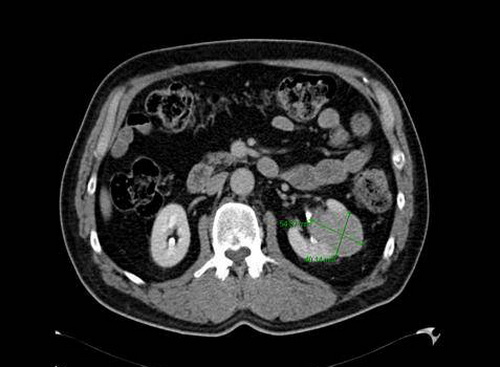

CT-Niere

Linke Niere: Inhomogene Raumforderung etwa 5 × 4 cm ø. Kein Hinweis auf eine Harntransportstörung, keine Konkremente